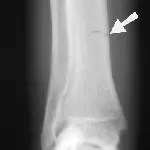

Figure 5A. An obvious fracture is not seen on this lateral radiographic view of the radius and ulna.

A radiograph shows a lateral view of a dog's forelimb, highlighting a fracture in the radius just above the carpal joint, indicated by an arrow. The surrounding bone structure appears intact, and the fracture line is clearly visible.

Figure 5B. A nondisplaced hairline fracture of the distal radius (arrow) that involves the medial cortex of the distal radius is easily seen, demonstrating the need for multiple radiographic views.